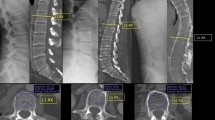

Quantification of whole spine CT

Whole spine CT was performed twice per patient: once at baseline and then again 2 years later. Patients were placed in a supine position and scanned using a 64-slice CT scanner (GoldSeal Optima CT 660; GE healthcare, Chicago, IL, USA). A volume CT with 0.625 mm acquisition was acquired from the superior endplate of C1 down to the coccyx (120 kVp, 213 mAs, 110 mm/s, 1.375:1 helical pitch). Next, sagittal and coronal plane views including the complete vertebral column were reconstructed from 2 mm slices. Two independent readers scored the whole spine CT images using the CTSS6 and the sCTSS. The CTSS, which ranges from 0 to 552 was calculated as described previously6. The sCTSS used only sagittal plane CT images, and divided each vertebral corner into anterior and posterior aspects. The degree of syndesmophyte formation was scored as follows: 0, no syndesmophytes; 1, syndesmophytes, but not bridging; and 2, total ankylosis (bridging). The details are described in Supplementary Table 1, and example of scoring is presented in Supplementary Fig. 1. The CTSS and sCTSS were measured independently by two readers at baseline and at the 2-year follow-up. Both readers were blinded to all patient information and the dates were removed from the scans; the scans were then presented to the readers as Digital Imaging and Communication in Medicine files.